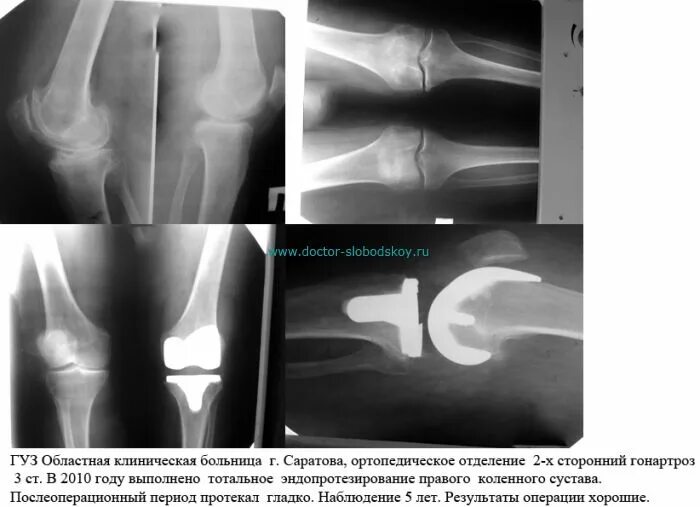

Нестабильность коленного сустава симптомы